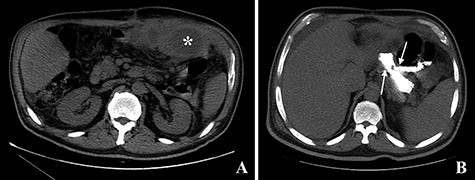

The computed tomography (CT) scan with oral contrast revealed a GGF (see Fig. 1). The upper gastrointestinal endoscopy confirmed a GGF and also demonstrated a stenosis of the gastro-jejunal anastomosis (GJA) (see Fig. 2).

Computed tomography with intravenous contrast images demonstrating a gastro-gastric fistula (arrows). A: axial reconstruction; B: sagittal reconstruction.

Computed tomography images. A: Image obtained prior to administration of contrast showing an abscess on the left upper quadrant of the abdomen (asterisk). B: Image obtained after administration of oral contrast showing progression of contrast through the gastro-jejunal anastomosis and through the gastro-gastric fistula (arrows).